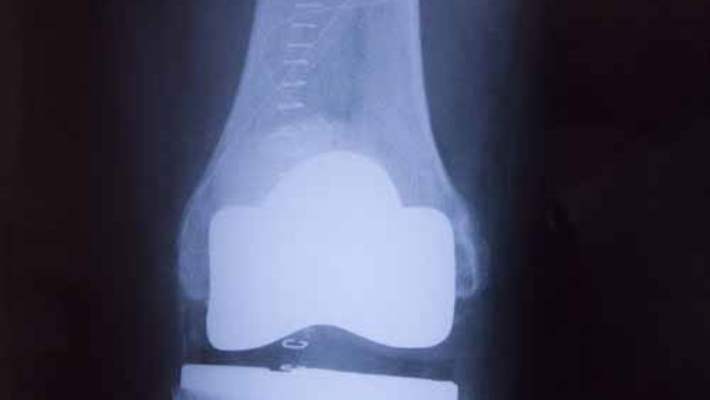

Konuşma ve muayene sonrası ön diz ağrılarının nedenlerini ve ciddiyetini tesbit için çeşitli radyolojik incelemeler gerekir. Diz kapağının pozisyonunu saptamak için diz kapağının çeşitli açılarda pozisyon röntgenleri, bilgisayarlı tomografi istenebilir. Diz kapağı ve altındaki kıkırdağın durumunun tesbiti ve diz içindeki-tendonlardaki diğer patolojilerin tesbiti için de MR sıklıkla gerekir.

- 1. Artroskobik cerrahi; 2 adet 1 cm den küçük kesilerden cerrahi yapılır. Artroskopi ile bozulmuş kıkırdak parçalarının traşlanması-canlandırılması yapılabilir. Artroskopik veya bazen 2 cm lik küçük kesiler eklenerek kıkırdak nakilleri yapılabilmektedir. (miniopen teknik)

- Diz kapağının dışa devrik veya yarı çıkık olduğu durumlarda diz kapağını dışa doğru çeken kapsül artroskobik olarak kesilerek (LATERAL GEVŞETME) pozisyonunun düzeltilmesi sağlanır. Diz kapağının pozisyonunun tam düzelmediği durumlarda içteki kapsülün daraltılması da eklenebilmektedir.

2. Yönlendirme cerrahisi; Artroskopinin başarılı olmadığı veya diz kapağının ileri çıkık-yarı çıkık durumlarında diz kapağının anatomik kusurunu düzeltici kemik operasyonları gerekebilir. Bu konuda en popüler operasyon "Fulkerson Osteotomisi" dir. Bu operasyonda diz kapağı kemiğinin alt bağlantısı patellar tendonun tibiaya yapışma yerinin içe-öne-yukarı veya aşağı kaydırma olanağı vardır. Böylece diz kapağı pozisyonu düzelmiş ve kıkırdağına binen aşırı yükler azaltılmış olur. Ameliyat sonrası ciddi bir fizik tedavi gereksinimi vardır.